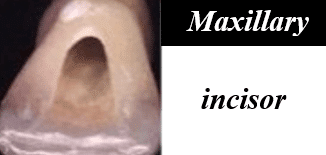

Shapes of the access cavity of all teeth

| Tooth | Access cavity shape | Average depth |

|---|---|---|

| Maxillary incisors | Triangular or oval (placed over the palatal surface) |

3-4 mm |

ROOT CANALS

| Tooth type | Common number of roots & canals | Variations |

|---|---|---|

| Maxillary central incisor | 1 root 1 canal |

Rare: 2 canals (vertucci type II). |

| Maxillary lateral incisor | 1 root 1 canal |

Rare: 2 canals (type II). Dens invaginatus. |